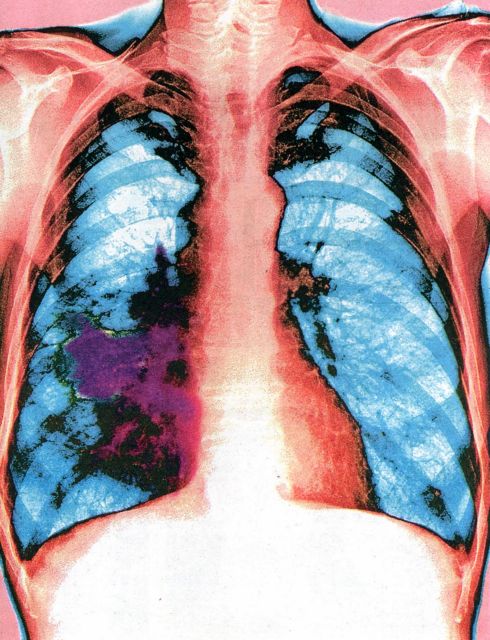

Η κύρια αιτία θανάτου από καρκίνο παγκοσμίως είναι αυτός του πνεύμονα. Κάθε χρόνο 1,59 εκατομμύρια άνθρωποι χάνουν τη ζωή τους εξαιτίας της νόσου.

Αυτό μεταφράζεται σε περισσότερους από 4.350 θανάτους παγκοσμίως καθημερινά. Σύμφωνα με τους ειδικούς επιστήμονες, ο καρκίνος του πνεύμονα διακρίνεται γενικά σε δύο μεγάλες κατηγορίες: στον μη μικροκυτταρικό και στον μικροκυτταρικό καρκίνο του πνεύμονα. Ο μη μικροκυτταρικός καρκίνος του πνεύμονα είναι ο πιο συχνός τύπος και αφορά στο 85% των περιστατικών.